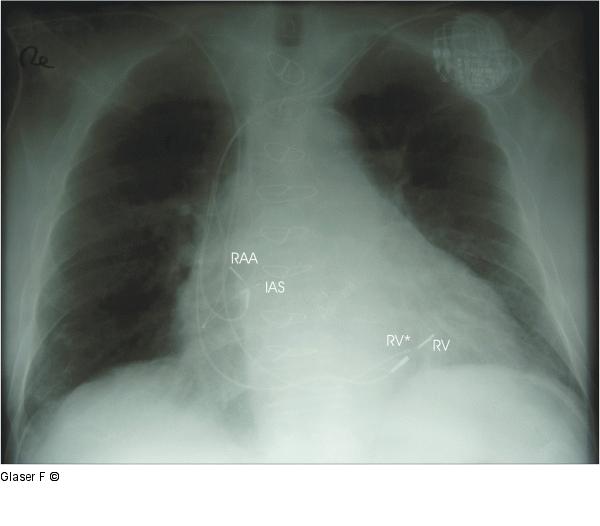

Abbildung 9: PA-Röntgen PA-Röntgen. IAS: Atrial-hochseptal in der Nähe des Bachmann’schen Bündels geschraubte Elektrode. RAA: abisolierte Ankerelektrode im rechten Herzohr, RV: Weiterverwendete rechtsventrikuläre Elektrode, RV*: Chronisch stillgelegte rechtsventrikuläre Elektrode. |

Abbildung 9: PA-Röntgen